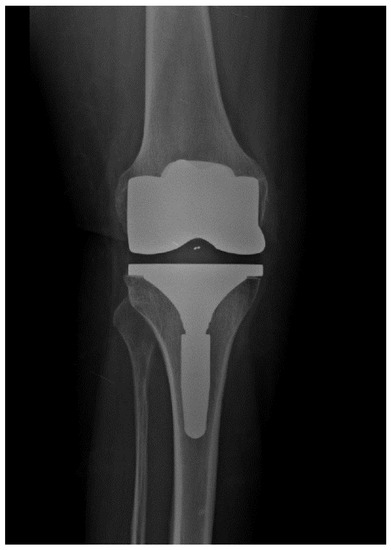

Titanium-Nitride Coating Does Not Result in a Better Clinical Outcome Compared to Conventional Cobalt-Chromium Total Knee Arthroplasty after a Long-Term Follow-Up: A Propensity Score Matching Analysis

Hauer, G.; Leitner, L.; Ackerl, M.C.; Klim, S.; Vielgut, I.; Ehall, R.; Glehr, M.; Leithner, A.; Sadoghi, P. Titanium-Nitride Coating Does Not Result in a Better Clinical Outcome Compared to Conventional Cobalt-Chromium Total Knee Arthroplasty after a Long-Term Follow-Up: A Propensity Score Matching Analysis. Coatings 2020, 10, 442. https://doi.org/10.3390/coatings10050442